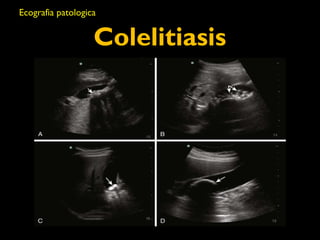

Colelitiasis

• Caracteristicas ecograficas

• Estructuras ecogénicas dentro de la luz

vesicular libre de ecos

• Sombra acustica con margenes “limpios”

• Dependencia gravitacional

• Son usualmente moviles

• Patrones de imagenes

• Foco ecogénico, sombra acustica limpia,

dependencia gravitacional

• Gravedad

• Lito grande

• Signo de eco de la pared